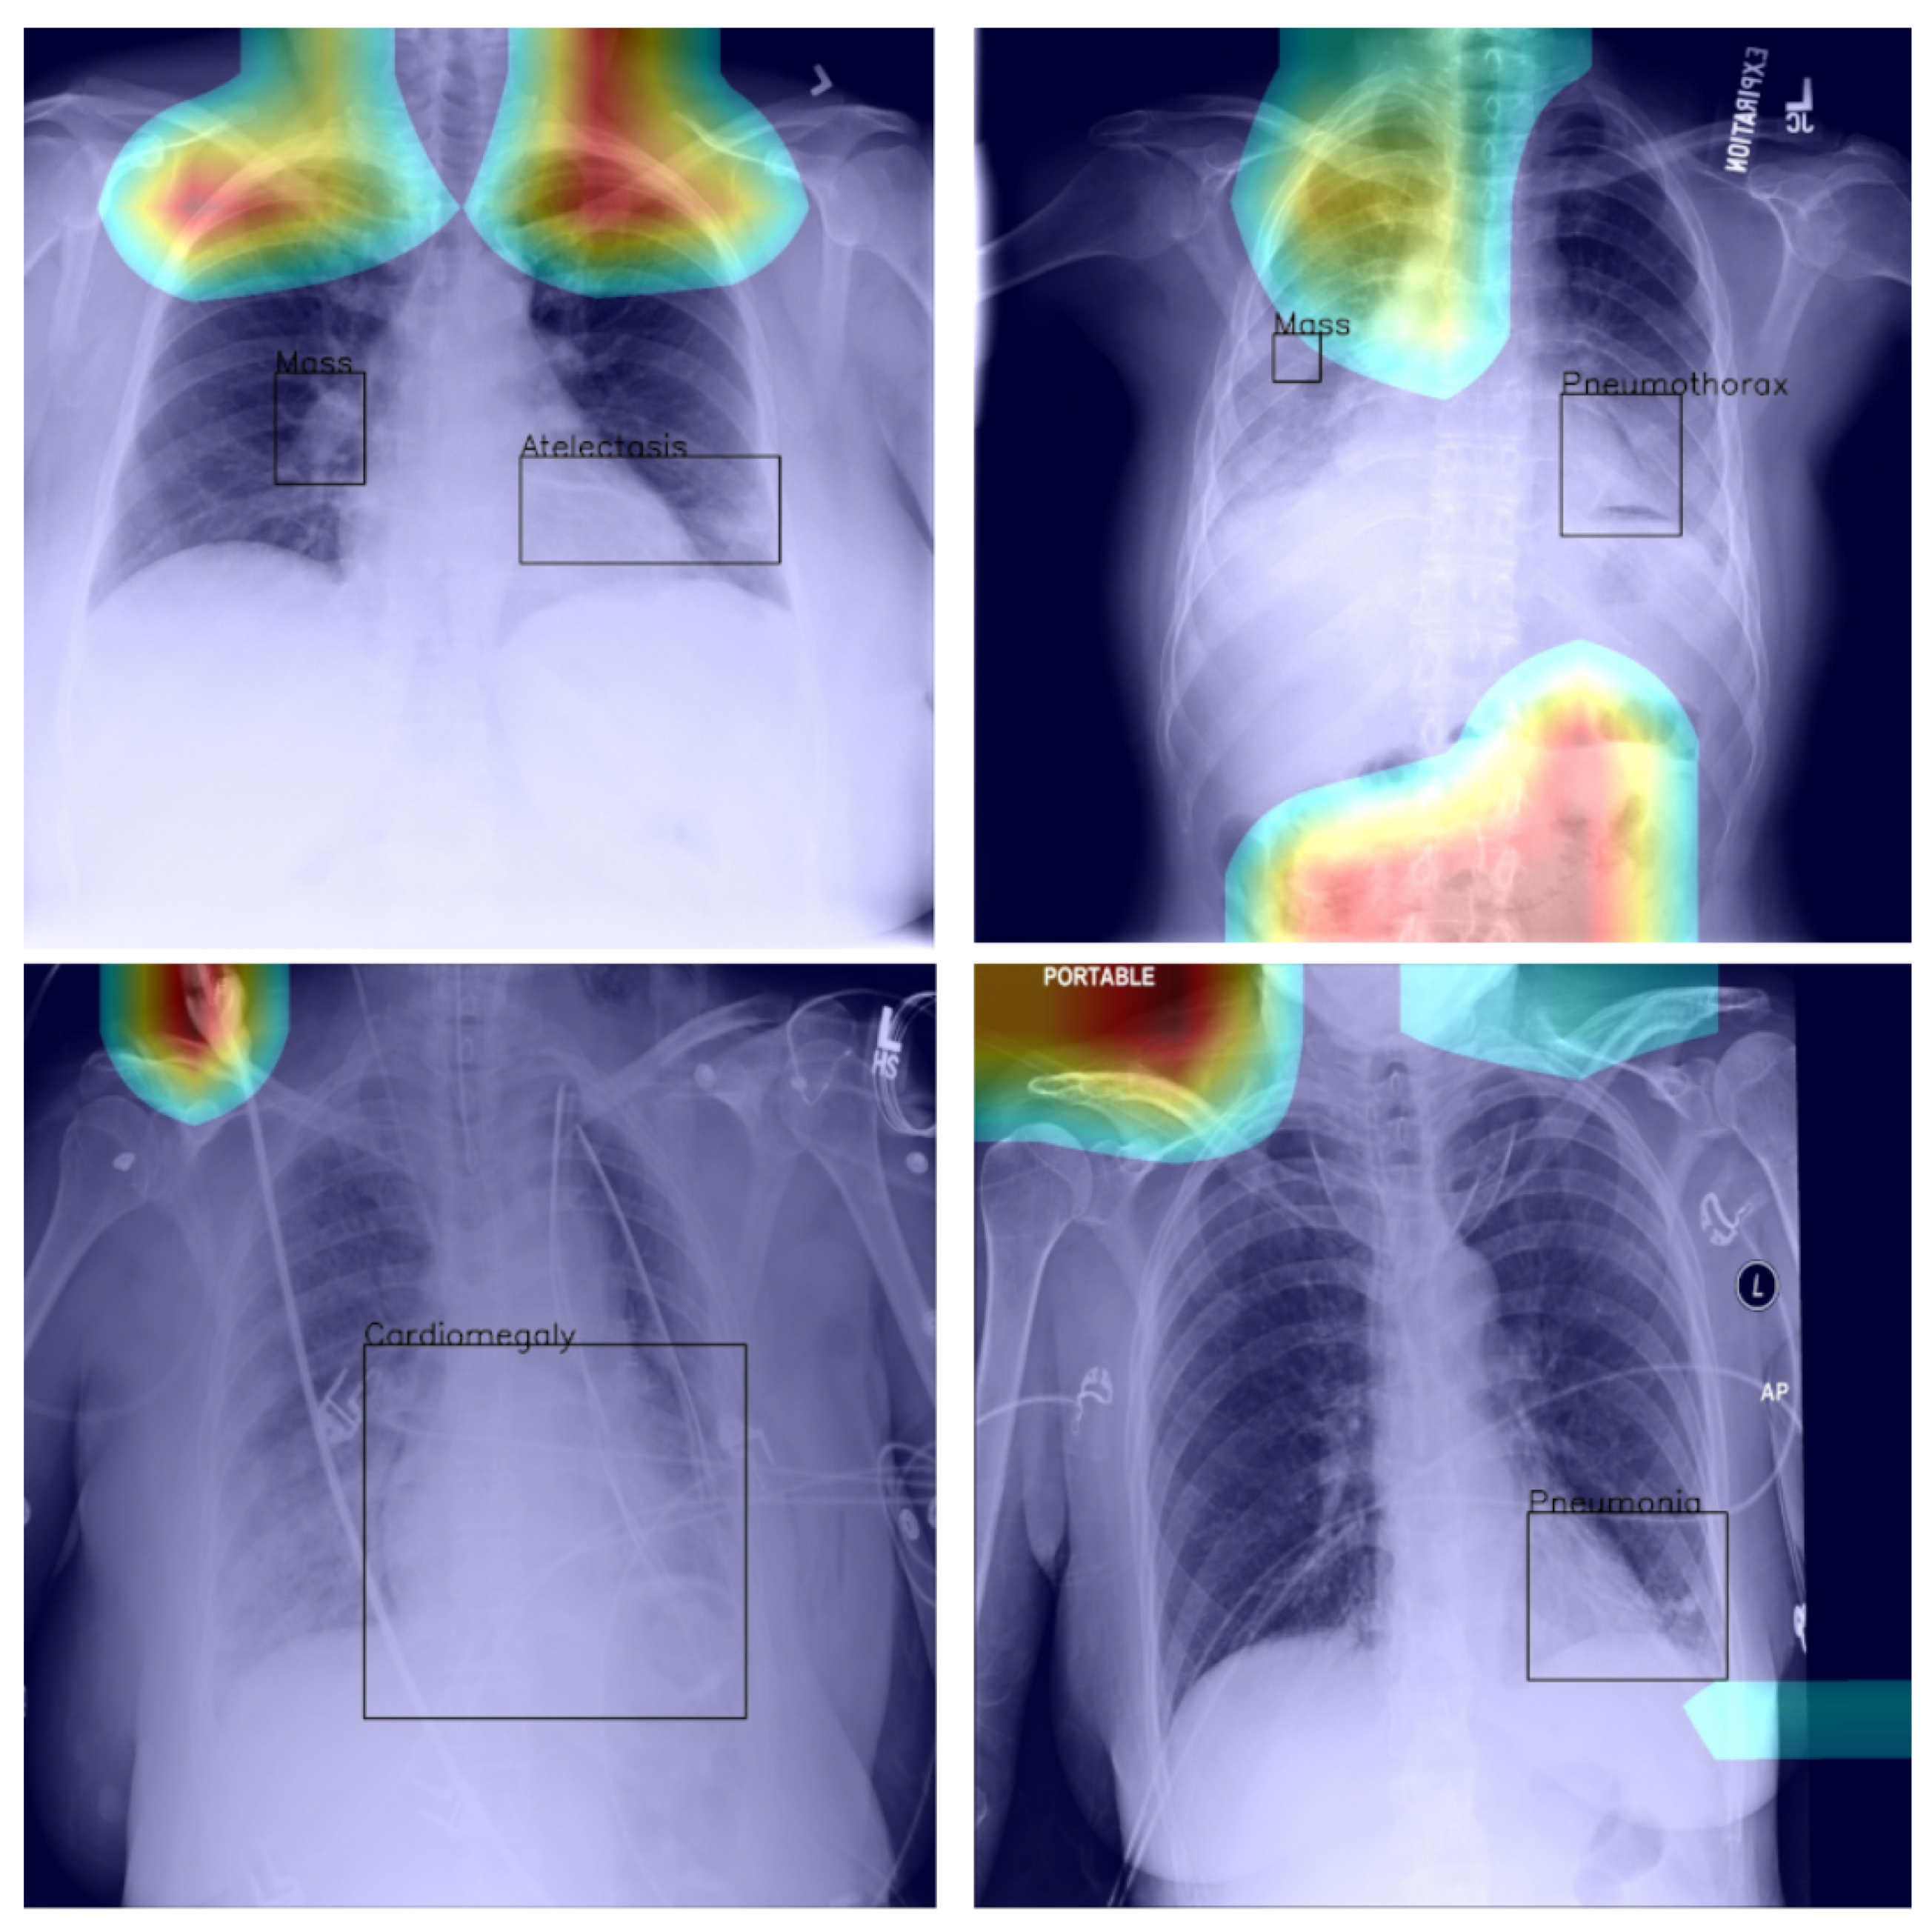

4.4. Saliency and Explainability

As we noted previously, using Grad-CAM, or indeed similar methods [27], it is possible to quantify and thus visualise the importance of different parts of an analysed image a network uses as the basis for its prediction. This can be helpful both in understanding why the model fails when it does as well in focusing an expert’s attention for further analysis and interpretation.

Using the bounding boxes information provided, we further examined how well the models performed in localizing the visual presentation of different diseases. We quantified this using the intersection over union (IoU), a ratio of the intersection of the bounding box and heat map activation and the union of the area they both cover, which can be loosely related to the well-known Bhattacharyya coefficient, a measurement of the amount of overlap between two statistical samples [28,29]. The ratio was calculated using thresholded heat maps with the key findings summarised in Table 6 and Table 7.

These findings are interesting in the context of the previously discussed AUROC-based comparison. Although the modified model performed better in terms of the former performance measure, that is to say AUROC, here, we found that it is the standard that does a better job in localizing the diseases. The likely explanation for this apparent paradox can be found in the structure of the network that was introduced in Section 3 and shown in Figure 1 and the flow of the metadata information and the manner in which it is used in the backpropagation. In any event, the important lesson to draw here is the same one that pervades the present article: any model must be examined in a variety of different ways and its performance measured using a range of comprehensive metrics and with a keen eye on their clinical significance, and its failure modes must be identified and understood, before any application in the real world is even considered.

Returning to the findings in Table 6 and Table 7, it is a concerning fact that the minimum IoU for all classes was found to be zero (an interesting example is shown in Figure 4. In other words, in the case of every class, that is disease, there was at least one instance in which the ground truth bounding box had no intersection with the thresholded saliency heat map. The models did, however, perform rather well in many cases, as indicated by the average scores. To check for potential biases, we measured the Pearson’s correlation coefficient between the number of class instances and the corresponding mean IoU and found it to be −0.265. This is an interesting and perhaps somewhat surprising finding, which should be revisited in future work. On the present evidence, we hypothesise that the more numerous classes exhibited greater variability in appearance presentation, which affected the performance under the IoU measure.

Figure 4.

Example of a high-confidence correct label identification, despite the entirely incorrect disease localisation.

Last but not least, we found that when the heat map is significantly off course, this is often an indicator of there being confounding information—in the sense that it is not inherent information affected by imaging, but rather added by human experts such as radiologists and, as such, being assistive in correct labelling prediction, but misleading in the context of what the method is trying to achieve; see Figure 5—present in an image (e.g., various textual descriptors overlaid on the images). If unnoticed, such information can instil false confidence in the performance of a model. Thus, we were again drawn to make two conclusions and recommendations: it is important that confounds of this kind be explicitly stated, observed, and discussed in any research and that a thorough examination of the data and specific findings be made whenever an algorithm is evaluated.

Figure 5.

Examples of confounding information unwittingly aiding inference.